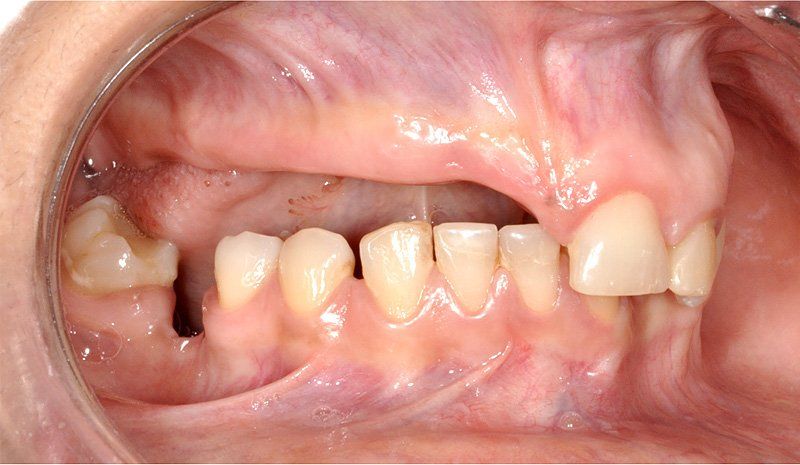

Los Implantes de Carga Inmediata son una solución práctica y definitiva para el desdentado total, es un tratamiento el cual una vez que se opera y se colocan los implantes, por un periodo entre 24 horas a 48 horas, se colocan los dientes en forma provisional, de esta forma el paciente queda con algo fijo mientras el implante se adhiere al hueso. Su principal ventaja radica en la reducción o eliminación del tiempo de espera entre la colocación del implante dental y la colocación de los dientes fijos.

Son recomendables para personas que no están dispuestas a una prótesis removible y quienes quieren acortar los tiempos de espera.